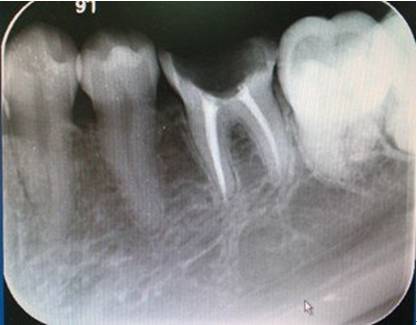

术前评估:通过X光片等检查,评估牙根的形态和根管数量。

术后复查:通过X光片检查根管充填效果,并根据需要调整治疗计划。